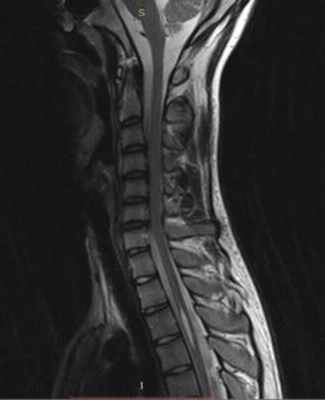

МРТ позволяет увидеть сирингомиелические полости и сопутствующее увеличение спинного мозга ( рис. 373.9 ). Во всех случаях проводят МРТ головного мозга и всех отделов спинного мозга, что позволяет установить распространенность полостей, оценить состояние образований задней черепной ямки и диагностировать гидроцефалию . Если причина сирингомиелии не ясна, то проводят МРТ с контрастированием. Это позволяет обнаружить опухоль спинного мозга, поскольку она накапливает контрастное вещество.

МРТ изображение (T2-взвешенное изображение) кранио-вертебрального перехода и шейного отдела позвоночника. Определяется комбинированный порок развития (аномалия Киари и платибазия), который привел к нарушению циркуляции ликвора в области большой затылочной цистерны, в результате чего развилась сирингомиелия (синие стрелки).